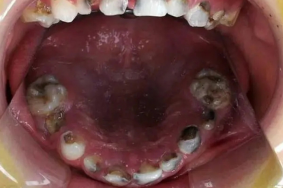

儿童龋齿的治疗

儿童蛀牙建议及时修补,避免龋坏更加严重。

两岁以后乳牙全部萌出,六周岁左右开始恒牙逐渐替代乳牙。在这期间儿童不注意口腔清洁,经常有食物残留,细菌就会腐蚀牙齿牙釉质形成蛀牙。